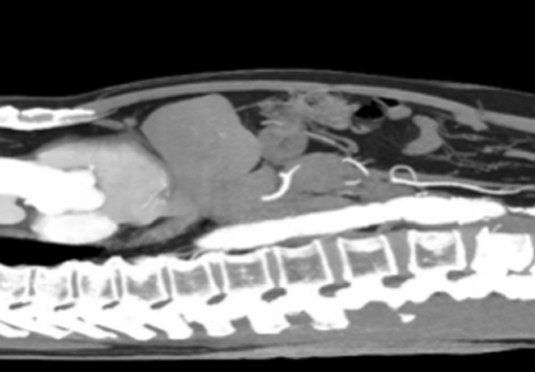

微創(chuàng)射頻消融術(shù)

適用于微創(chuàng)射頻熱消融術(shù)治療患者,引進(jìn)權(quán)威醫(yī)療團(tuán)體輔助引流。